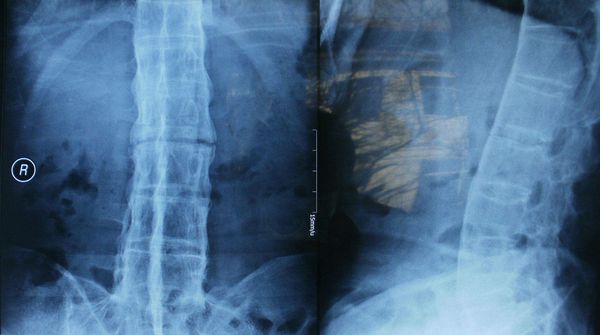

全脊柱正侧位显示骶髂关节间隙消失

脊柱竹节样融合改变